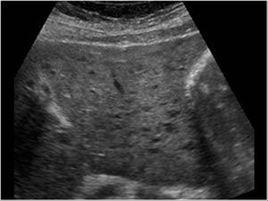

患者空腹8~12h以上,平臥位及左側臥位進行多切面掃查,觀察肝包膜、肝緣形態、肝實質回聲、肝靜脈走行及靜脈壁形態和膽囊、脾臟改變。

診斷標準:①肝靜脈走行呈自然弧度,壁平整為正常;壁不平整,粗細不均,蛇行,壁顯示不清為異常;介於二者之間為輕度異常;肝右靜脈內徑≥7mm為正常,4~6mm為輕度異常,≤3mm為狹窄。②肝表面回聲及形態:肝表面呈細線狀,被膜平整為正常,表面線狀,被膜輕度增厚,回聲增強為輕度異常,被膜明顯增厚增強,呈細水紋狀或節段狀為異常,呈波浪狀、凹凸不平為嚴重異常。③肝實質回聲:均勻細點狀回聲為正常,稍增粗、增強、欠均勻為輕度異常,增粗、增強、不均勻為異常,呈網路狀為嚴重異常。④肝緣形態:肝下緣銳角為正常,鈍角為異常,介於二者之間為輕度異常。⑤膽囊:壁細線狀為正常,毛糙為輕度異常,壁增厚,呈“雙邊征”或膽囊充盈不佳為異常。⑥脾臟:長徑≤100mm,邊緣銳利為正常,長徑101~120mm,邊緣稍圓鈍為輕度異常,長徑>120mm,厚度≥40mm,邊緣圓鈍為異常。具備①~④項中的輕度異常2項以上+⑤~⑥項中的輕度異常1項以上的即可診斷肝瀰漫性病變。